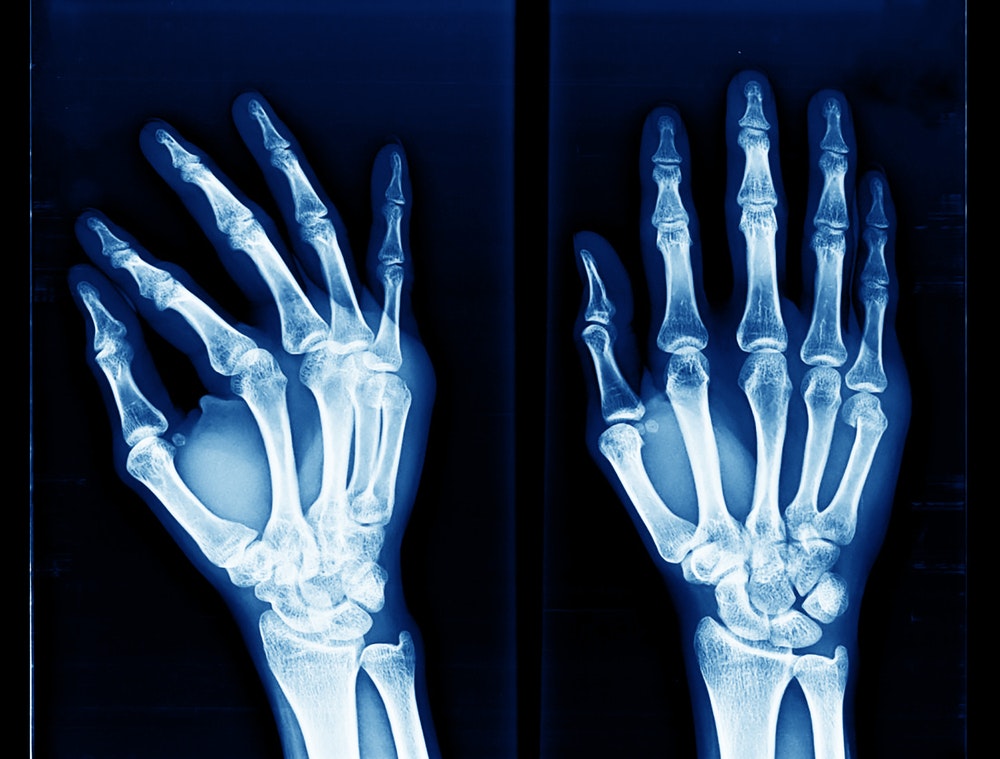

Using Advanced Imaging Technology

In addition to traditional X-rays, we may determine a computed tomography (CT) scan or a magnetic resonance imaging (MRI) scan is needed to help rule out injuries to the surrounding bones and ligaments. These images will also help Dr. Vagner determine the severity of your injury. After a full assessment, he will recommend appropriate care on a case-by-case basis.